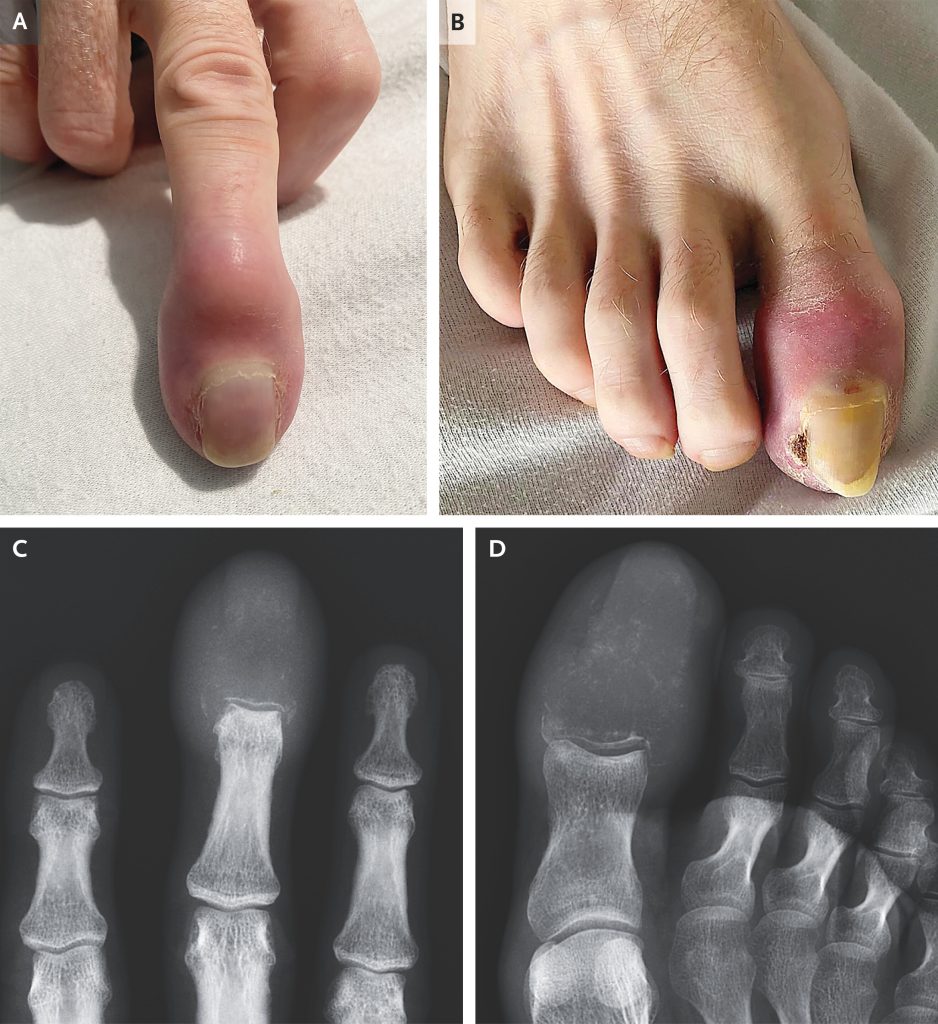

Totul a început aparent inofensiv: timp de șase săptămâni, degetele mijlociu și mare de la piciorul drept au început să se deformeze treptat, căpătând o formă ciudată, asemănătoare cu cea a unei „bâte de tobe”. Alarmat de evoluția simptomelor, bărbatul s-a prezentat la spital, unde medicii au descoperit mult mai mult decât un simplu edem. Extremitățile erau roșii, umflate și prezentau chiar un ulcer în apropierea unghiei.

Însă cele mai tulburătoare informații au venit de la investigațiile imagistice: oasele din degetele afectate erau complet distruse și fuseseră înlocuite de mase tumorale. Diagnosticul: acrometastază — o formă extrem de rară de metastază osoasă, care afectează oasele de la nivelul mâinilor sau picioarelor, sub coate și genunchi. Această formă reprezintă doar 0,1% din toate cazurile de metastaze osoase.

Pacientul suferea deja de un cancer pulmonar scuamos, în stadiu avansat, care se răspândise în întregul organism. În general, când celulele canceroase metastazează la nivel osos, ele preferă zonele bogate în măduvă osoasă, cum ar fi coloana vertebrală, coastele sau oasele lungi. În schimb, oasele mici ale degetelor, sărace în măduvă și slab vascularizate, sunt rar afectate — ceea ce explică raritatea acrometastazelor.